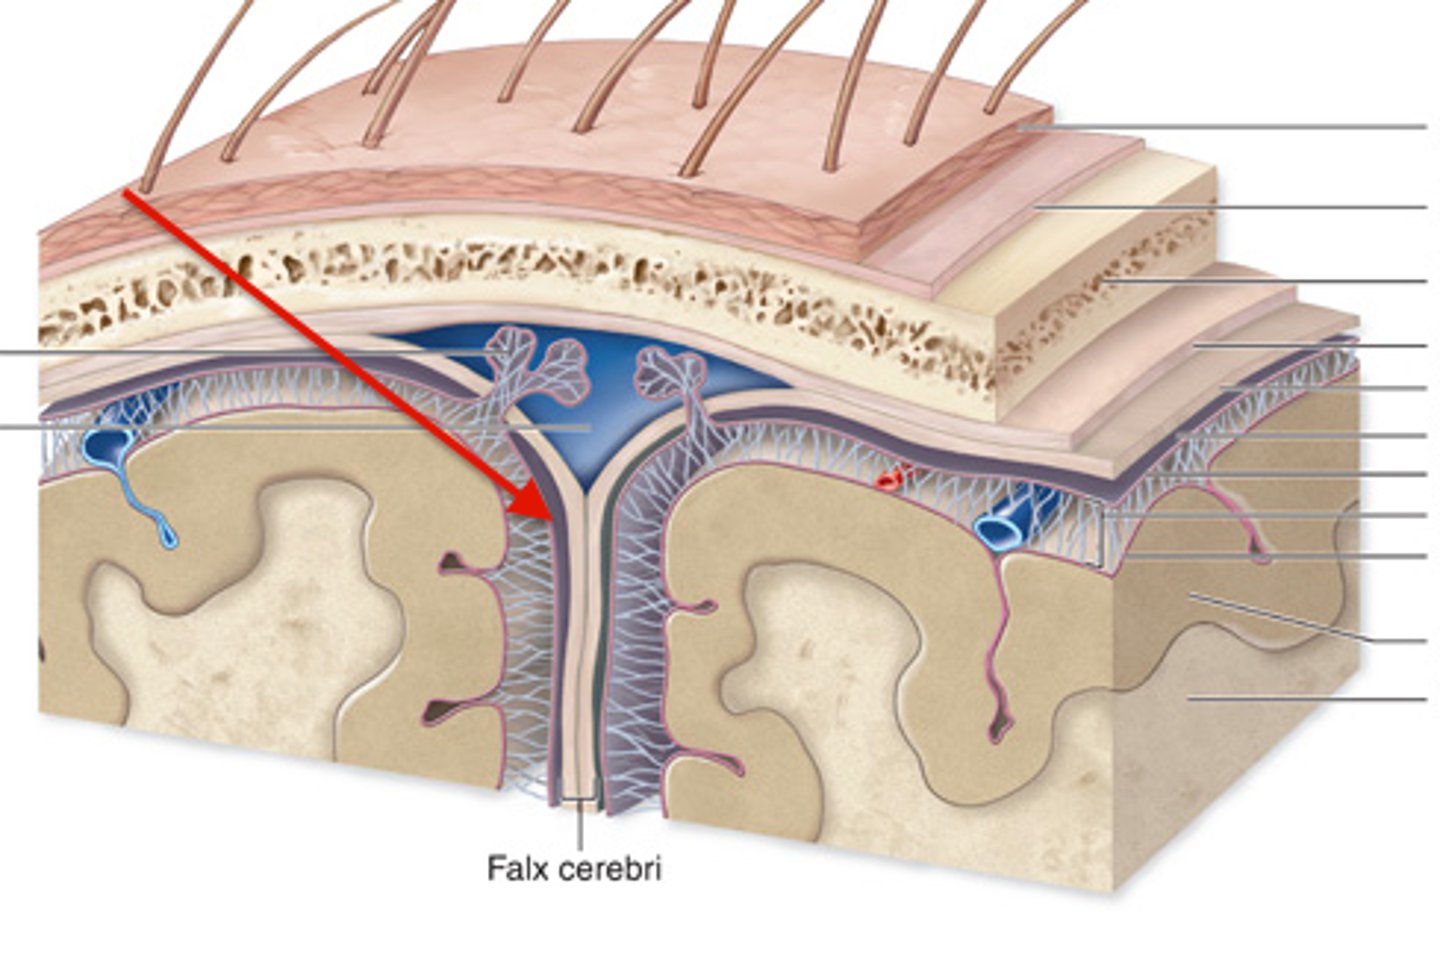

meninges function

protect brain and spinal cord

pia mater

deepest meninge, follows every contour of the brain

arachnoid mater

middle meninge, collagen and elastin fiber, spider web look

dura mater

made up of tough fibrous connective tissue, made up of the periosteal layer (creates periosteum of skull bone)

subarachnoid space

filled with cerebrospinal fluid

dural folds

Folded inner layer of dura mater

Extend into cranial cavity

Stabilize and support brain

subdural space

below the dura mater

potential space (if you have a head injury

the blood goes into the subdural space)

falx cerebri

separates the two hemispheres of the cerebrum

tentorium cerebelli

horizontal dural fold over cerebellum and in transverse fissure

falx cerebelli

separates the two hemispheres of the cerebellum